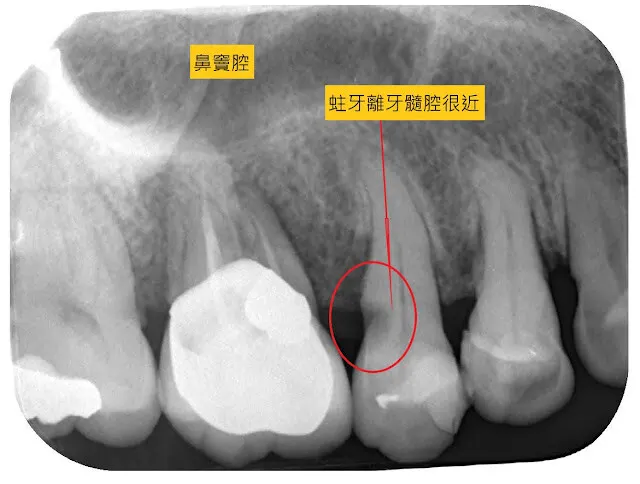

活髓治療的過程

何醫師寫的這篇,介紹的相當詳盡,所以直接沿用,我再補充一些細節。 建議用桌機網頁閱讀,圖片字跡才夠清楚。